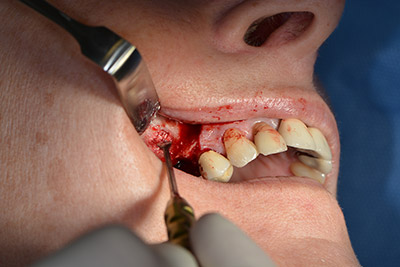

Danach wird das Implantat eingebracht und der Knochen aufgebaut. Aufgrund der Größe des Augmentates wurde im vorliegenden Fall Eigenknochen, der als Bohrspäne bei der Implantation 16 und der Fenestration 14 angefallen ist und mit einer Knochenfalle aufgefangen wurde, mit Knochenersatzmaterial vermischt.

Eine resorbierbare Membran bildet die Barriere nach bukkal und deckt das Augmentat ab. Zum Schluss wird speicheldicht vernäht. (Abb. 15 bis 19).